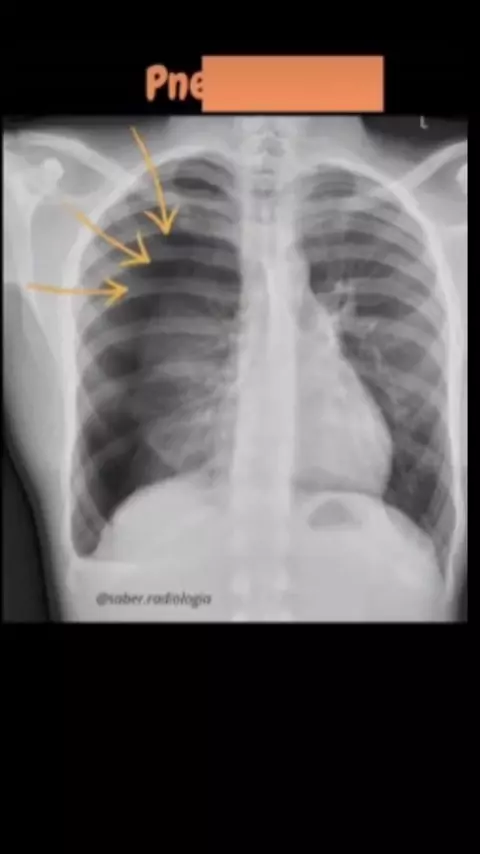

radiologia do pulmão #atelectasiadopulmao #pneumotorax #derramepleural #consolidacaopulmonar